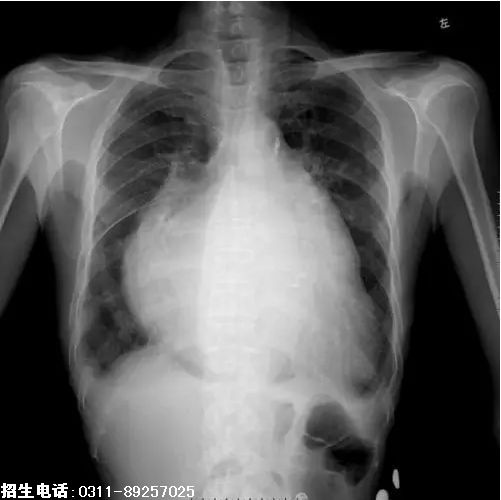

8、题干:女,65岁。劳力性呼吸困难进行性加重5天。结合X线片,此诊断为

答案:D

解析:由X线可知,该患者心影普遍增大,心室和心房均有明显的扩张,为普大型心。(D对)